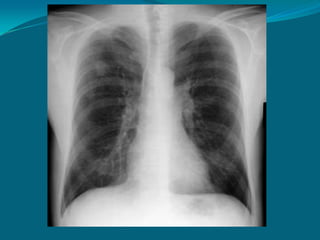

Rx PA normal y con

técnica adecuada:

PENETRACIÓN:

Los cuerpos vertebrales

inferiores son visibles

ROTACIÓN:

Las apófisis espinosas

son centrales respecto a

las articulaciones

esternoclaviculares

INSPIRACIÓN:

La parte posterior de la

10° u 11° costilla se

encuentran cerca del

ángulo cardiofrénico